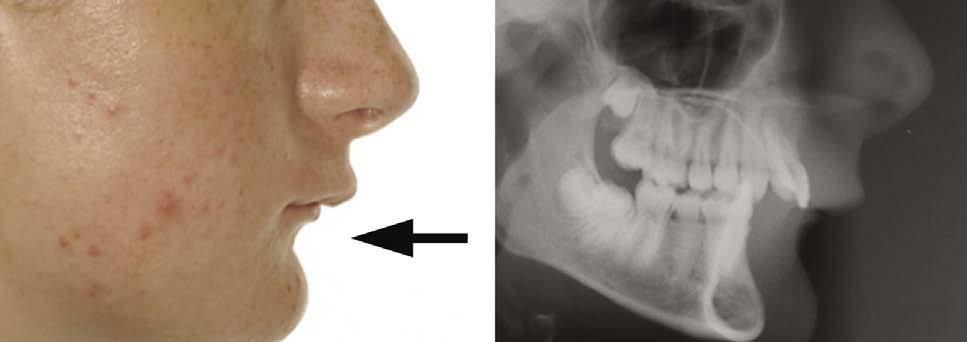

Children with nasopharyngeal obstruction associated with enlarged adenoids have been shown to have longer faces and smaller mandibles compared to controls (Fig. 1.9) (Linder-Aronson, 1970).

Figure 1.9 Child with increased facial height and lip incompetence with a history of nasal blockage and mouth breathing. This appearance has been described as an adenoidal face.

Overproduction of growth hormone from an anterior pituitary tumour causes gigantism in children and acromegaly in adults. In both circumstances, the patient presents with a worsening class III malocclusion characterized by mandibular excess (Fig. 1.13).

An inflammatory arthritis occurring before the age of 16 years and involving the temporomandibular joints can result in the development of a severe class II malocclusion due to restricted growth of the mandible (Fig. 1.12).

Figure 1.12 Lateral skull radiograph of patient with a history of juvenile rheumatoid arthritis.